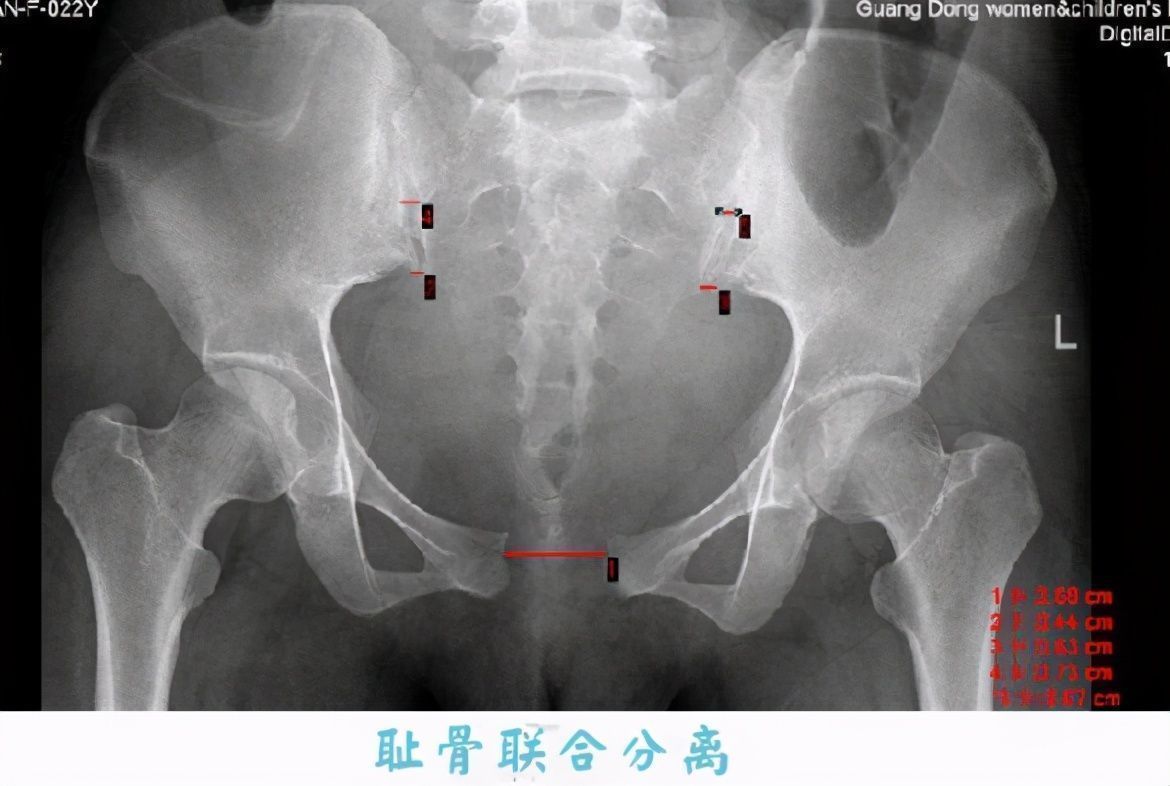

从这张图上可以看出,正常的耻骨几乎是连接在一起的,而孕晚期耻骨联合处会出现分离的现象,正如你说看到的,有两块骨头在分离。

一般来说,孕晚期两块耻骨会分离到0.3-0.4厘米,而耻骨分离的时候会刺激到痛觉神经,所以就产生了疼痛。当然耻骨分离也是有原因的,这是为了宝妈能更容易分娩。我当初耻骨痛的时候,婆婆就在一旁说,越痛越好生产。虽然耻骨疼痛的程度跟生产之间没有必然联系,但是耻骨分离的确是为了让孕妈更好分娩。